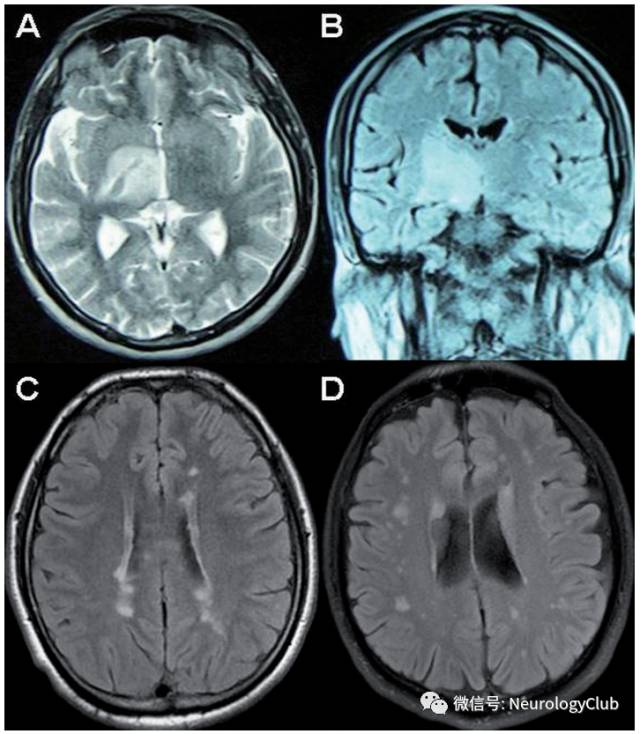

(图16:A-B:典型实质病变,从间脑延伸至基底节;C:多发性硬化样病灶;D:非特异性白质病变)